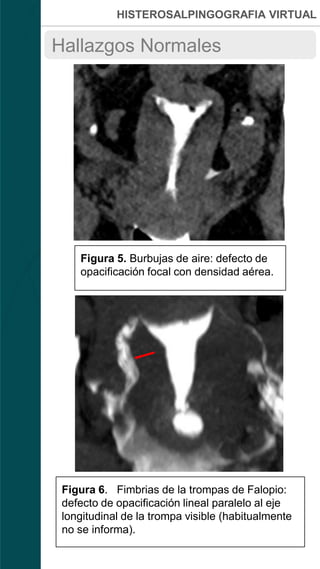

Figura 5. Burbujas de aire: defecto de

opacificación focal con densidad aérea.

Figura 6. Fimbrias de la trompas de Falopio:

defecto de opacificación lineal paralelo al eje

longitudinal de la trompa visible (habitualmente

no se informa).